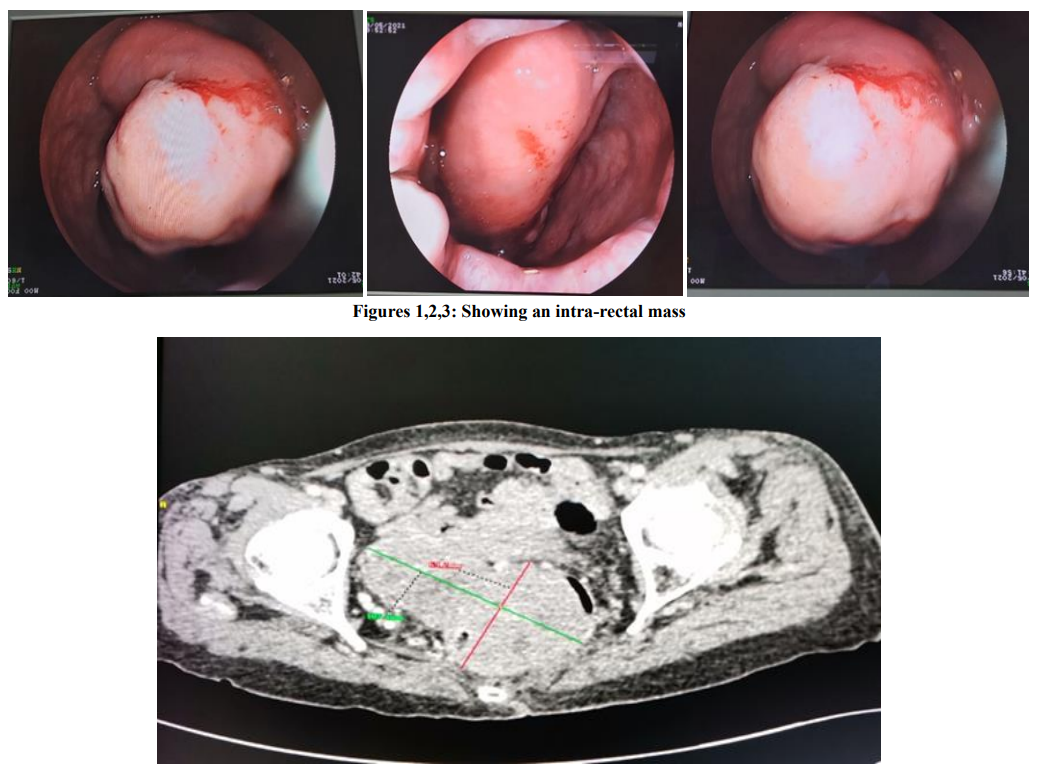

Anorectal Gastrointestinal Stromal Tumor: About a Rare Case Report and Review of Literature

Aouroud Hala, Jihane Rizkou, Khadija Krati

International Journal of Innovative Research in Medical Science·October 28, 2022